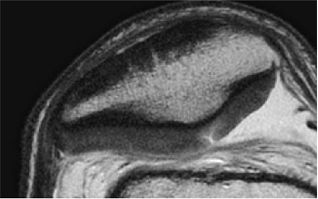

to minimize chemical shift misregistration as well as to reduce inter-echo spacing. Decreasing inter-echo spacing will minimize the edge blurring routinely encountered with fast spin-echo techniques performed at correspondingly narrower bandwidths with wider inter-echo spacing. The effect of chemical shift causes a misregistration at the interface between fat (subchondral bone) and water (cartilage), resulting in factitious loss of the subchondral plate, abnormal signal hyperintensity in the adjacent cartilage (due to the frequency shift summation), and inaccurate assessment of cartilage morphology (Fig. 7.7).

FIGURE 7.7 ● Sagittal fast spin-echo MR images of the knee in a 28-year-old man performed on a high-field system (3 Tesla). (A) There is chemical shift misregistration and image blurring at a receiver bandwidth of 10 kHz (arrowhead). (B) Corresponding image acquisition with all parameters held the same except for the use of a wider receiver bandwidth of 62.5 kHz. Attention to imaging technique is imperative to provide reproducible cartilage imaging.